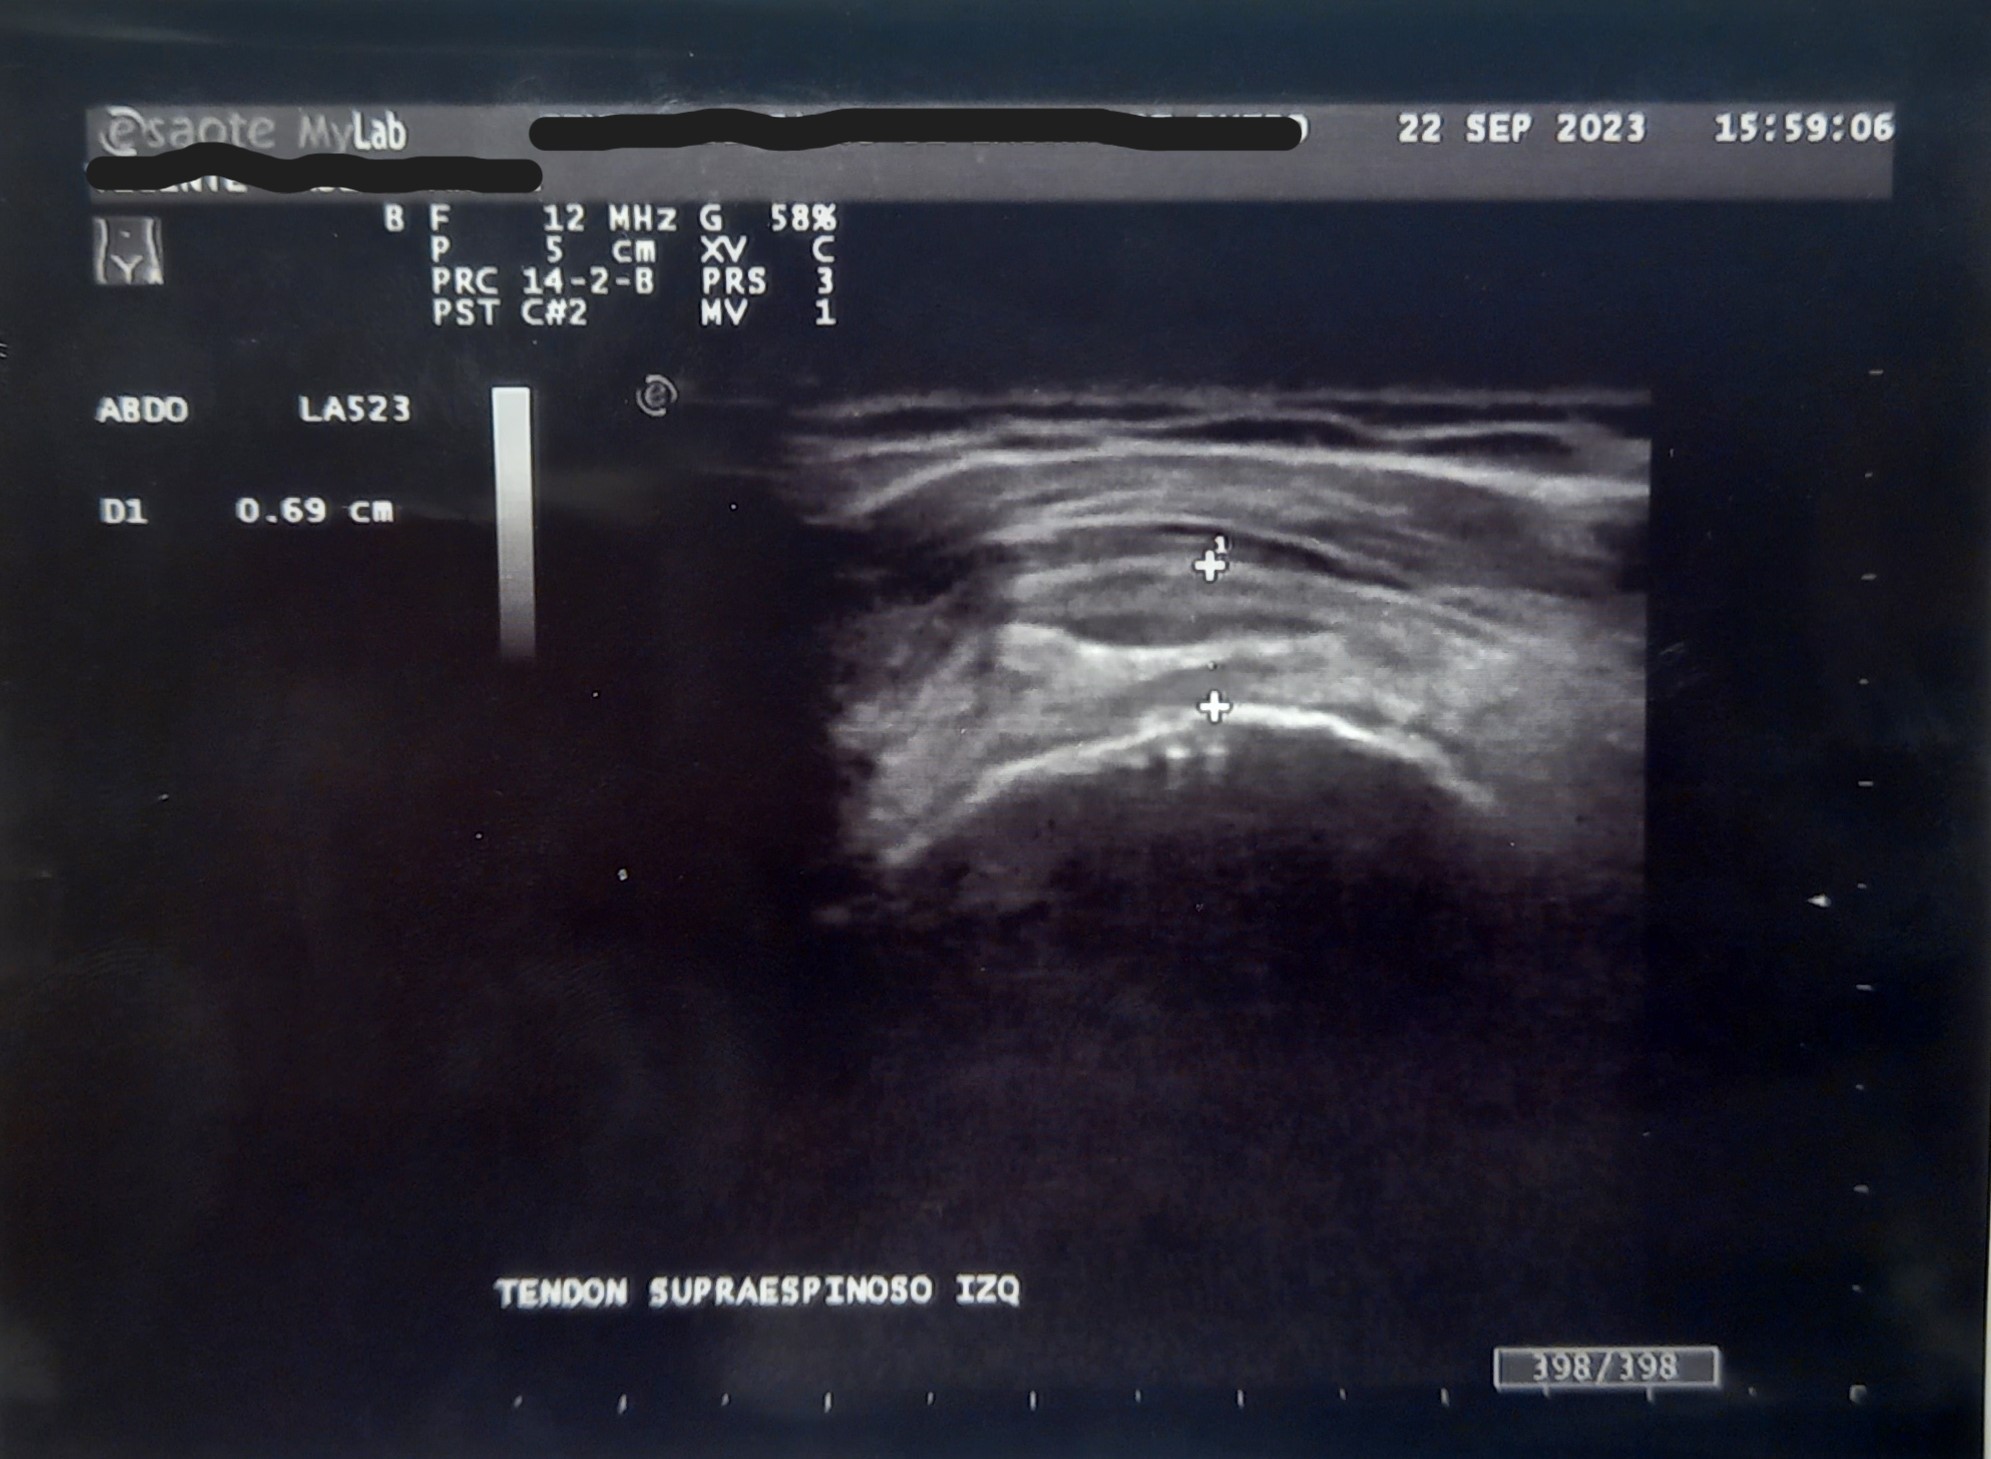

Hallazgos ecográficos

Ecografía en consulta de Atención Primaria. Se observa en la ecografía de partes blandas Patrón heterogéneo en región de tendón supraespinoso, con áreas hipo ecoicas y banda hiperecogenica compatible con tendinitis calcificante del tendón del supraespinoso. Tendón sub-escapular con áreas hipoecoicas en su trayecto que puede atribuirse a tendinosis de larga evolución.